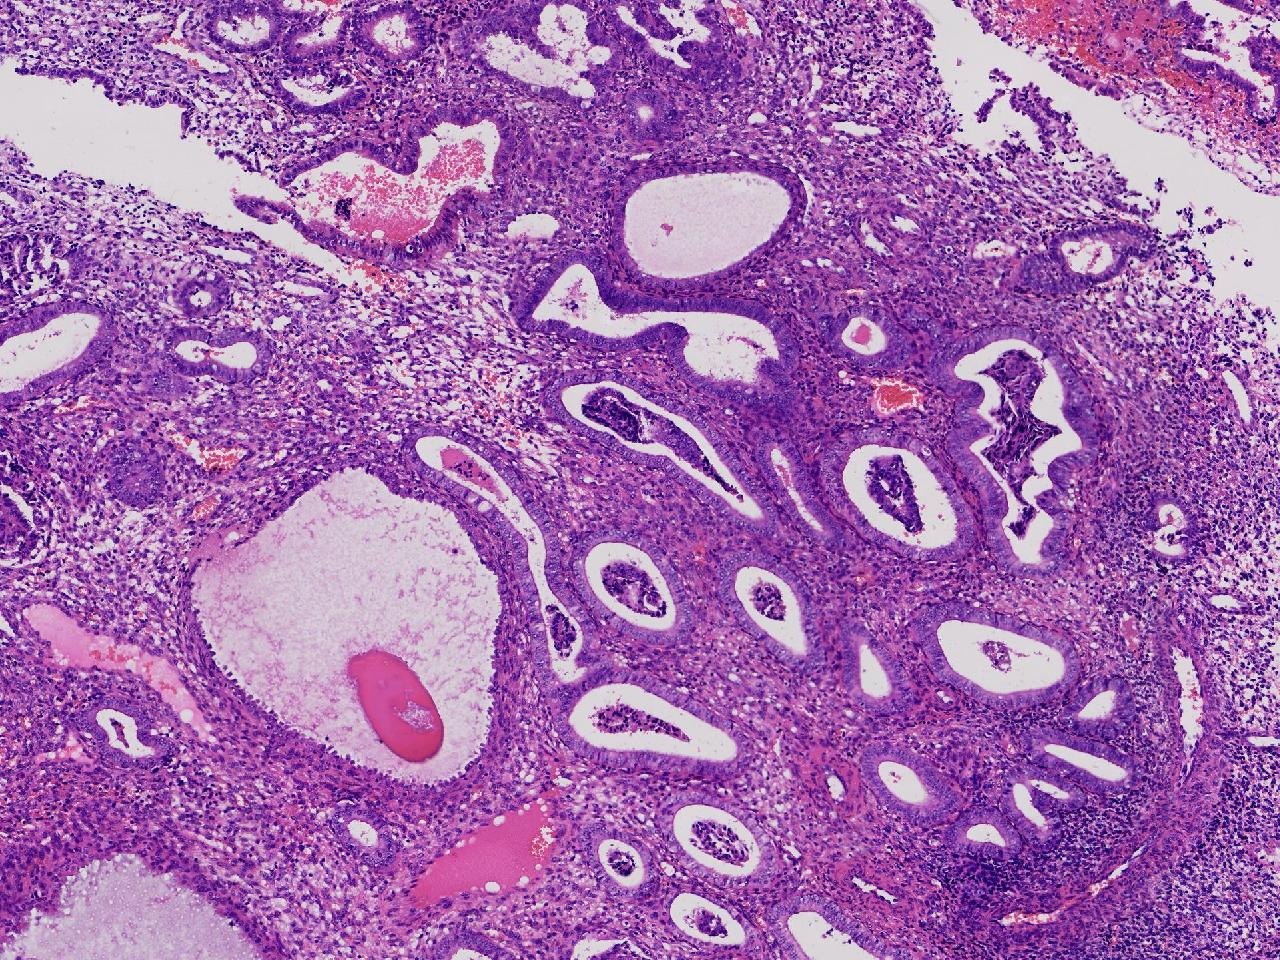

性别

女

年龄

55岁

女,55岁,月经紊乱4年,彩超示:子宫内膜增厚(内膜厚15.7mm),末次月经:2025年7月27日。

标本名称

宫腔镜下子宫内膜活检

大体所见

灰粉色不整形软组织多块,1.5X0.8X0.6厘米。

考虑:子宫内膜增生伴子宫内膜炎

子宫内膜增生紊乱,内膜息肉样结构